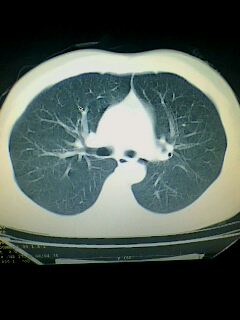

标题: CT28315:咳嗽咳痰咯血半月并胸痛 [打印本页]

标题: CT28315:咳嗽咳痰咯血半月并胸痛

考虑左肺下叶周围型肺癌.图象欠清,请问病人贵更?

考虑左肺下叶周围型肺癌.

图像资料欠清,建议强化,考虑周围型肺癌。